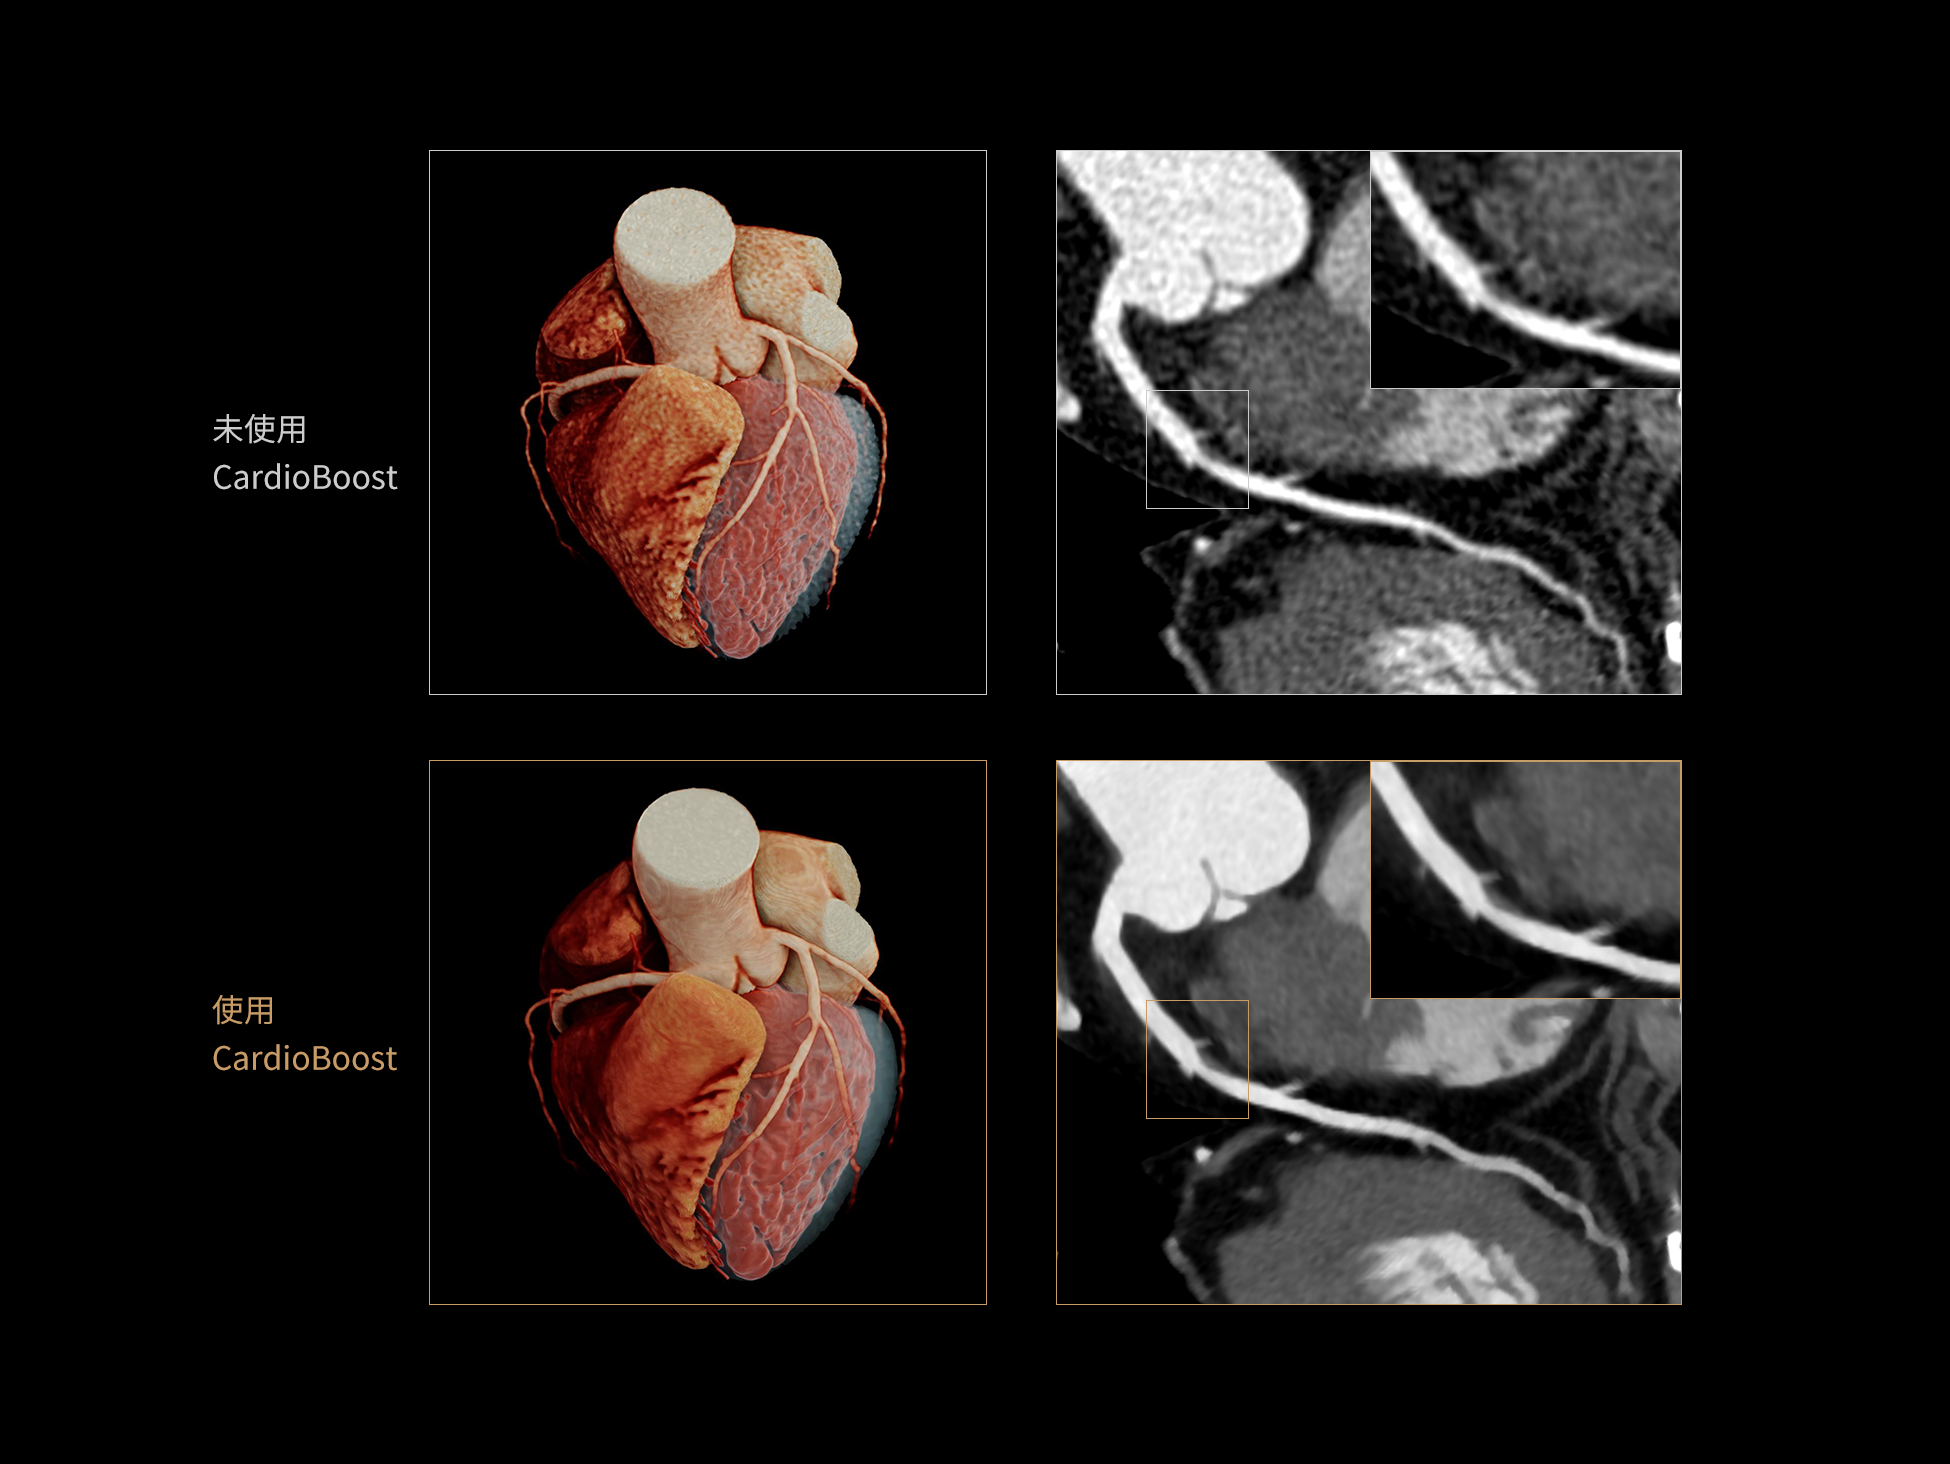

CardioBoost:专属网络设计,重塑心脏影像表现

目前心脏的 CT 检查还存在辐射剂量偏高、空间分辨率不足、 致密钙化伪影影响冠脉狭窄程度评估等方面的限 制[1][2]。CardioBoost 技术专为心脏 CT 高清成像而开发,通过 3D 神经网络的深度学习技术,利用先进的注意力机制在识别关键成像特征方面的出色表现,能够精确地聚焦于斑块、支架以及微小血管等关键细节,清晰展示这些结构与冠脉血管的边界,从而显著提高诊断的准确性,并提升医生的诊断信心。创新的 CardioBoost 心脏图像重建算法,不仅实现了图像清晰度的提升和伪影的去除,更能在减少辐射剂量的同时,保证心脏图像的高质量和图像纹理的自然。

采用 3D 神经网络的空间结构优势与精细的组织分类能力,CardioBoost 技术优化了组织对比,高清展示血管斑块,使斑块与血管边缘的轮廓清晰可辨,提升斑块诊断与评估的精确性。

借助 3D 神经网络设计、空间注意力机制聚焦与特征强化作用,CardioBoost技术提升图像的空间分辨率,实现冠脉支架的高清成像,对支架形态与管腔通畅度的评估更精准。

CardioBoost 整合先进的 3D 神经网络和空间注意力机制,大幅增强数据处理的速度与精确度。该技术能有效抑制由致密钙化引起的晕状伪影,清晰展现钙化斑块的原始结构和大小,对冠脉狭窄的评估更加精确可靠。

对比度强化模块

分辨率强化模块

伪影抑制模块